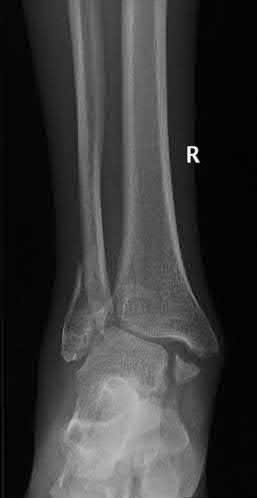

Question 9:

A 30-year-old male sustains a severe midfoot sprain. Radiographs reveal widening between the bases of the first and second metatarsals. The primary ligamentous stabilizer disrupted in this classic Lisfranc injury connects which two osseous structures?

Correct Answer: Medial cuneiform to 2nd metatarsal base

Explanation:

The Lisfranc ligament is the strongest ligament in the tarsometatarsal joint complex. It courses obliquely from the lateral aspect of the medial cuneiform to the medial base of the second metatarsal. It acts as the primary stabilizer of the second metatarsal base. Disruption results in the classic widening between the first and second rays, often with an avulsion fragment ('fleck sign').